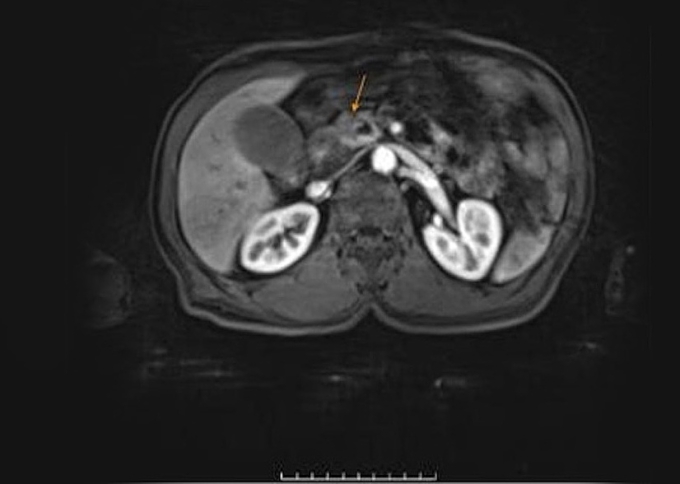

Sau vài tuần uống thuốc khi chỉ số men gan tăng cao, da và củng mạc mắt chuyển sang màu vàng, ông Quang đến Bệnh viện Đa khoa Tâm Anh TP HCM khám. Kết quả xét nghiệm cho thấy men gan của ông Quang cao hơn 30 lần so với bình thường, trong đó ALT (GPT) lên tới 1.600 U/L (bình thường khoảng 50 U/L). Chụp CT tụy và MRI ổ bụng ghi nhận tổn thương tại vùng đầu tụy kích thước khoảng 20 mm, chèn ép và xâm lấn túi tụy, giãn ống tụy 7 mm, thành túi mật phù nề, ống mật chủ giãn trong và ngoài gan.

Tổn thương bất thường ở vùng đầu tụy trên ảnh CT. Ảnh Bệnh viện Đa khoa Tâm Anh